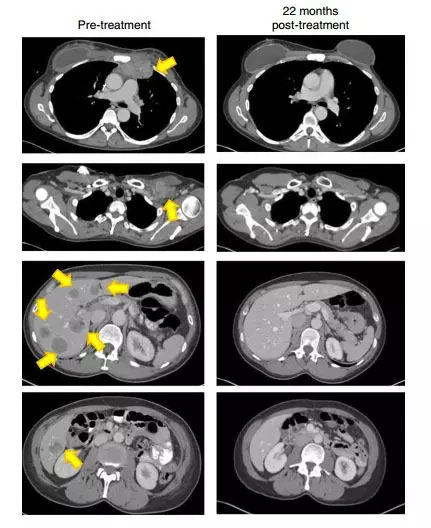

当900亿个免疫细胞被输入患者体内后,奇迹出现了,在6个月后的第一次随访时,患者的目标肿瘤负担锐减一半,而在治疗后的第22个月,从医学影像上看,所有肿瘤都消失了!

22个月后,这名患者的肿瘤(黄色箭头)消失得无影无踪(图片来源:《Nature Medicine》)